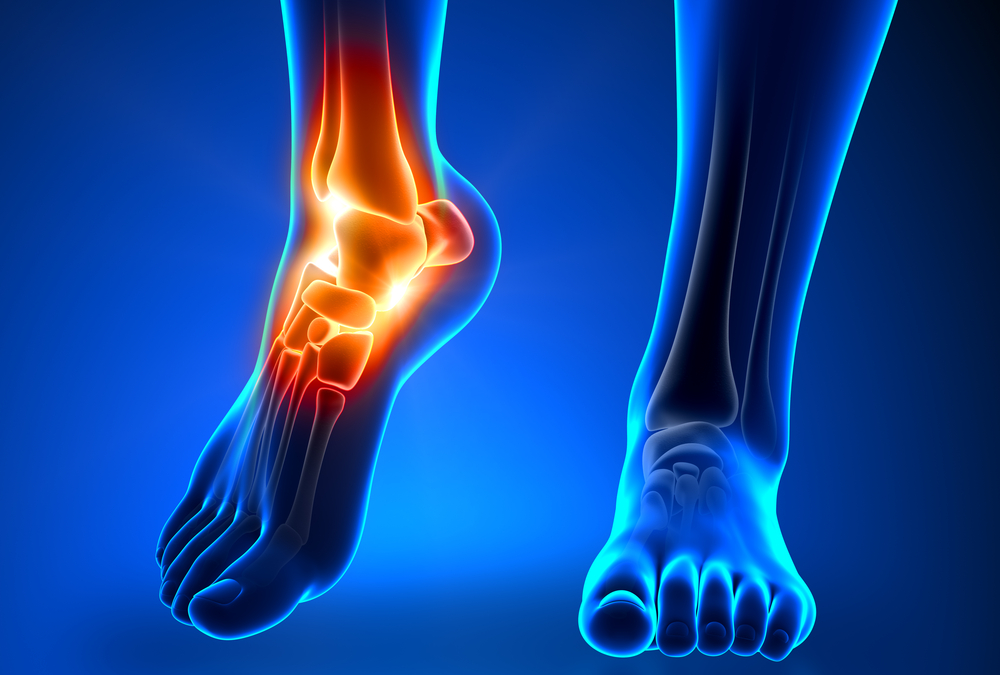

As we grow older, suffering from arthritis in the foot is one of the most common pains that many people face at some point in their life. Joints and tendons throughout your body begin to show signs of wear and tear from their use and exertion over the years, leading...

How Long Does It Take for Achilles Bursitis to Heal?

by jbaker@support.websitepro.hosting | Dec 1, 2021 | Blog

The Achilles tendon attaches the calf muscle to the heel bone. The bursa are what cushions this tendon, and when these fluid-filled sacs become inflamed, the result can be painful. If you have been diagnosed with Achilles Bursitis, the recovery period can vary. At...